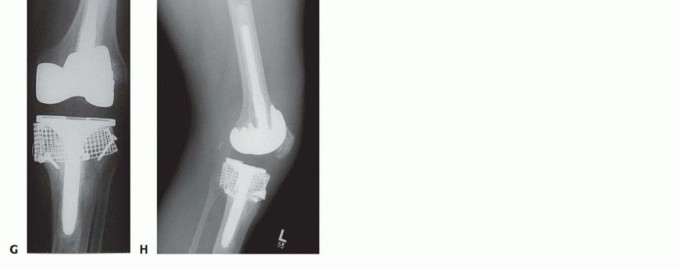

Zonal Fixation and Stem Implantation

Regardless of the grafting technique utilized, the definitive implant must achieve rigid stability. Diaphyseal engaging stems are mandatory when massive bone grafting is performed. The stem must bypass the grafted area by a minimum of two cortical diameters into the intact diaphysis.

Cementless, fluted, tapered stems are widely favored as they provide excellent rotational stability and immediate rigid fixation in the diaphysis. The metaphyseal portion of the implant, resting on the bone graft, is typically cemented. Care must be taken to prevent cement extrusion between the structural allograft and the host bone interface, as this will mechanically block biological incorporation and lead to graft nonunion. Offset stems may be required to accommodate the mismatch between the center of the diaphyseal canal and the center of the tibial plateau, ensuring optimal coverage of the reconstructed metaphysis.